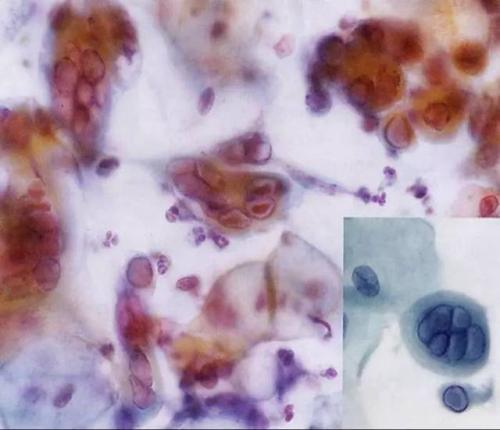

最近,1歲的萌萌(化名)頭上忽然起了一些紅疙瘩,沒(méi)過(guò)多少天,紅疙瘩竟遍布寶寶全身,讓她奇癢難忍。除螨蟲(chóng)活動(dòng)與挖掘隧道疥螨寄生在宿主表皮角質(zhì)層的深處,以角質(zhì)組織和淋巴液為食,并以螯肢和前跗爪挖掘,逐漸形成一條與皮膚平行的蜿蜒隧道。隧道最長(zhǎng)可達(dá)10~15mm。以雌螨所挖的隧道最長(zhǎng),每隔一段距離有小縱向通道通至表皮。雄螨與后若蟲(chóng)亦可單獨(dú)挖掘,但極短,前若蟲(chóng)與幼蟲(chóng)則不能挖掘隧道,只生活在雌螨所挖的隧道中。雌螨每天能挖0.5~5mm,一般不深入到角質(zhì)層的下面。螨蟲(chóng)怎么治療螨蟲(chóng)對(duì)皮膚的危害:螨蟲(chóng)在皮膚里面吸取營(yíng)養(yǎng)成分,刺激毛細(xì)血管以及細(xì)胞組織,引向皮膚惡化。皮膚螨蟲(chóng)加速細(xì)小皺紋的產(chǎn)生,加速黃褐斑、雀斑、黑斑等色素沉著,還可導(dǎo)致粉刺、痘疤、痤瘡、皮膚粗糙、角質(zhì)變厚、形成凹凸皮膚。皮膚螨蟲(chóng)還能形成瘙癢癥、酒糟鼻以及紅臉、紅血絲等。螨蟲(chóng)怎么治療局部異物反應(yīng),引起局部炎性病變。如毛脂器官堵塞,刺激角質(zhì)層增生,毛囊擴(kuò)張,毛孔粗大,毛囊營(yíng)養(yǎng)不足,毛發(fā)脫落等病變。皮脂過(guò)度分泌,導(dǎo)致油光滿(mǎn)面。家人趕緊將她送到兒童醫(yī)院檢查,才發(fā)明;禍?zhǔn)椎準(zhǔn)?竟是棉被里的螨蟲(chóng)。專(zhuān)家提示,要想防螨蟲(chóng)叮咬,要多開(kāi)窗通風(fēng),不給螨類(lèi)成長(zhǎng)的機(jī)會(huì);棉被在用之前要晾曬。據(jù)萌萌的母親徐女士介紹,2周前,萌萌頭上開(kāi)端冒紅疙瘩,隨后頭、臉、手到處都長(zhǎng)出了紅疙瘩。她嚇得趕緊帶著女兒到兒童醫(yī)院檢查。該院皮膚科副主任羅曉燕診斷后發(fā)明,患兒的每個(gè)紅疙瘩都有綠豆大小,晶瑩透亮,皰頂有一針尖大小的雀斑,水皰的基底部皮膚鮮紅,初步判斷寶寶患的應(yīng)是丘疹性蕁麻疹,患病的起因可能是被棉被里的螨蟲(chóng)叮咬所致。羅曉燕表示,螨蟲(chóng)是一種肉眼看不見(jiàn)的小蟲(chóng)子,平時(shí)愛(ài);埋伏;在被子、枕頭、地毯、布藝沙發(fā)、草席上。每個(gè)人對(duì)螨蟲(chóng)的過(guò)敏水平不同,一些對(duì)螨蟲(chóng)過(guò)敏的人,受到螨蟲(chóng)叮咬,就輕易過(guò)敏,并產(chǎn)生紅疙瘩。據(jù)理解,幼嬰跟兒童是螨蟲(chóng)過(guò)敏癥狀極為重大的群體,他們皮膚嬌嫩,很輕易對(duì)螨蟲(chóng)有過(guò)敏反應(yīng)。10%的13到14歲的兒童患有塵螨過(guò)敏性鼻炎。當(dāng)你家寶寶在初秋季節(jié)皮膚呈現(xiàn)皮疹,奇癢無(wú)比,甚至開(kāi)端一直打噴嚏、流鼻涕,重大者哮喘發(fā)生,要警戒誤診為個(gè)別感冒咳嗽,可能恰是螨蟲(chóng)沾染了!羅曉燕提示寬大家長(zhǎng):要想防螨蟲(chóng)叮咬,首先要堅(jiān)持環(huán)境的衛(wèi)生;經(jīng)常晾曬被褥;假如不太陽(yáng),可用開(kāi)水淋燙,等晾干后再利用。